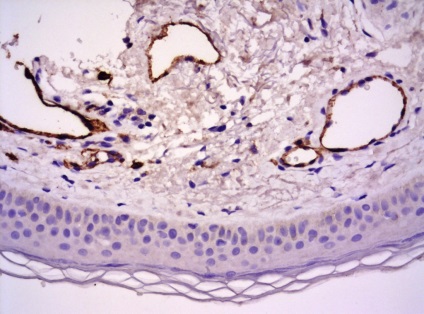

Ábra. Immunhisztokémia 11: CD-31 expressziója a vaszkuláris endotéliumon, a bőrben a haemangiomatosis

Következtetés (patológus MD Karev VE): egy jóindulatú daganat tömegének faggyúmirigy; haemangiomatosis bőrben, cutan vasculitis (gyulladásos elváltozások érfalak).